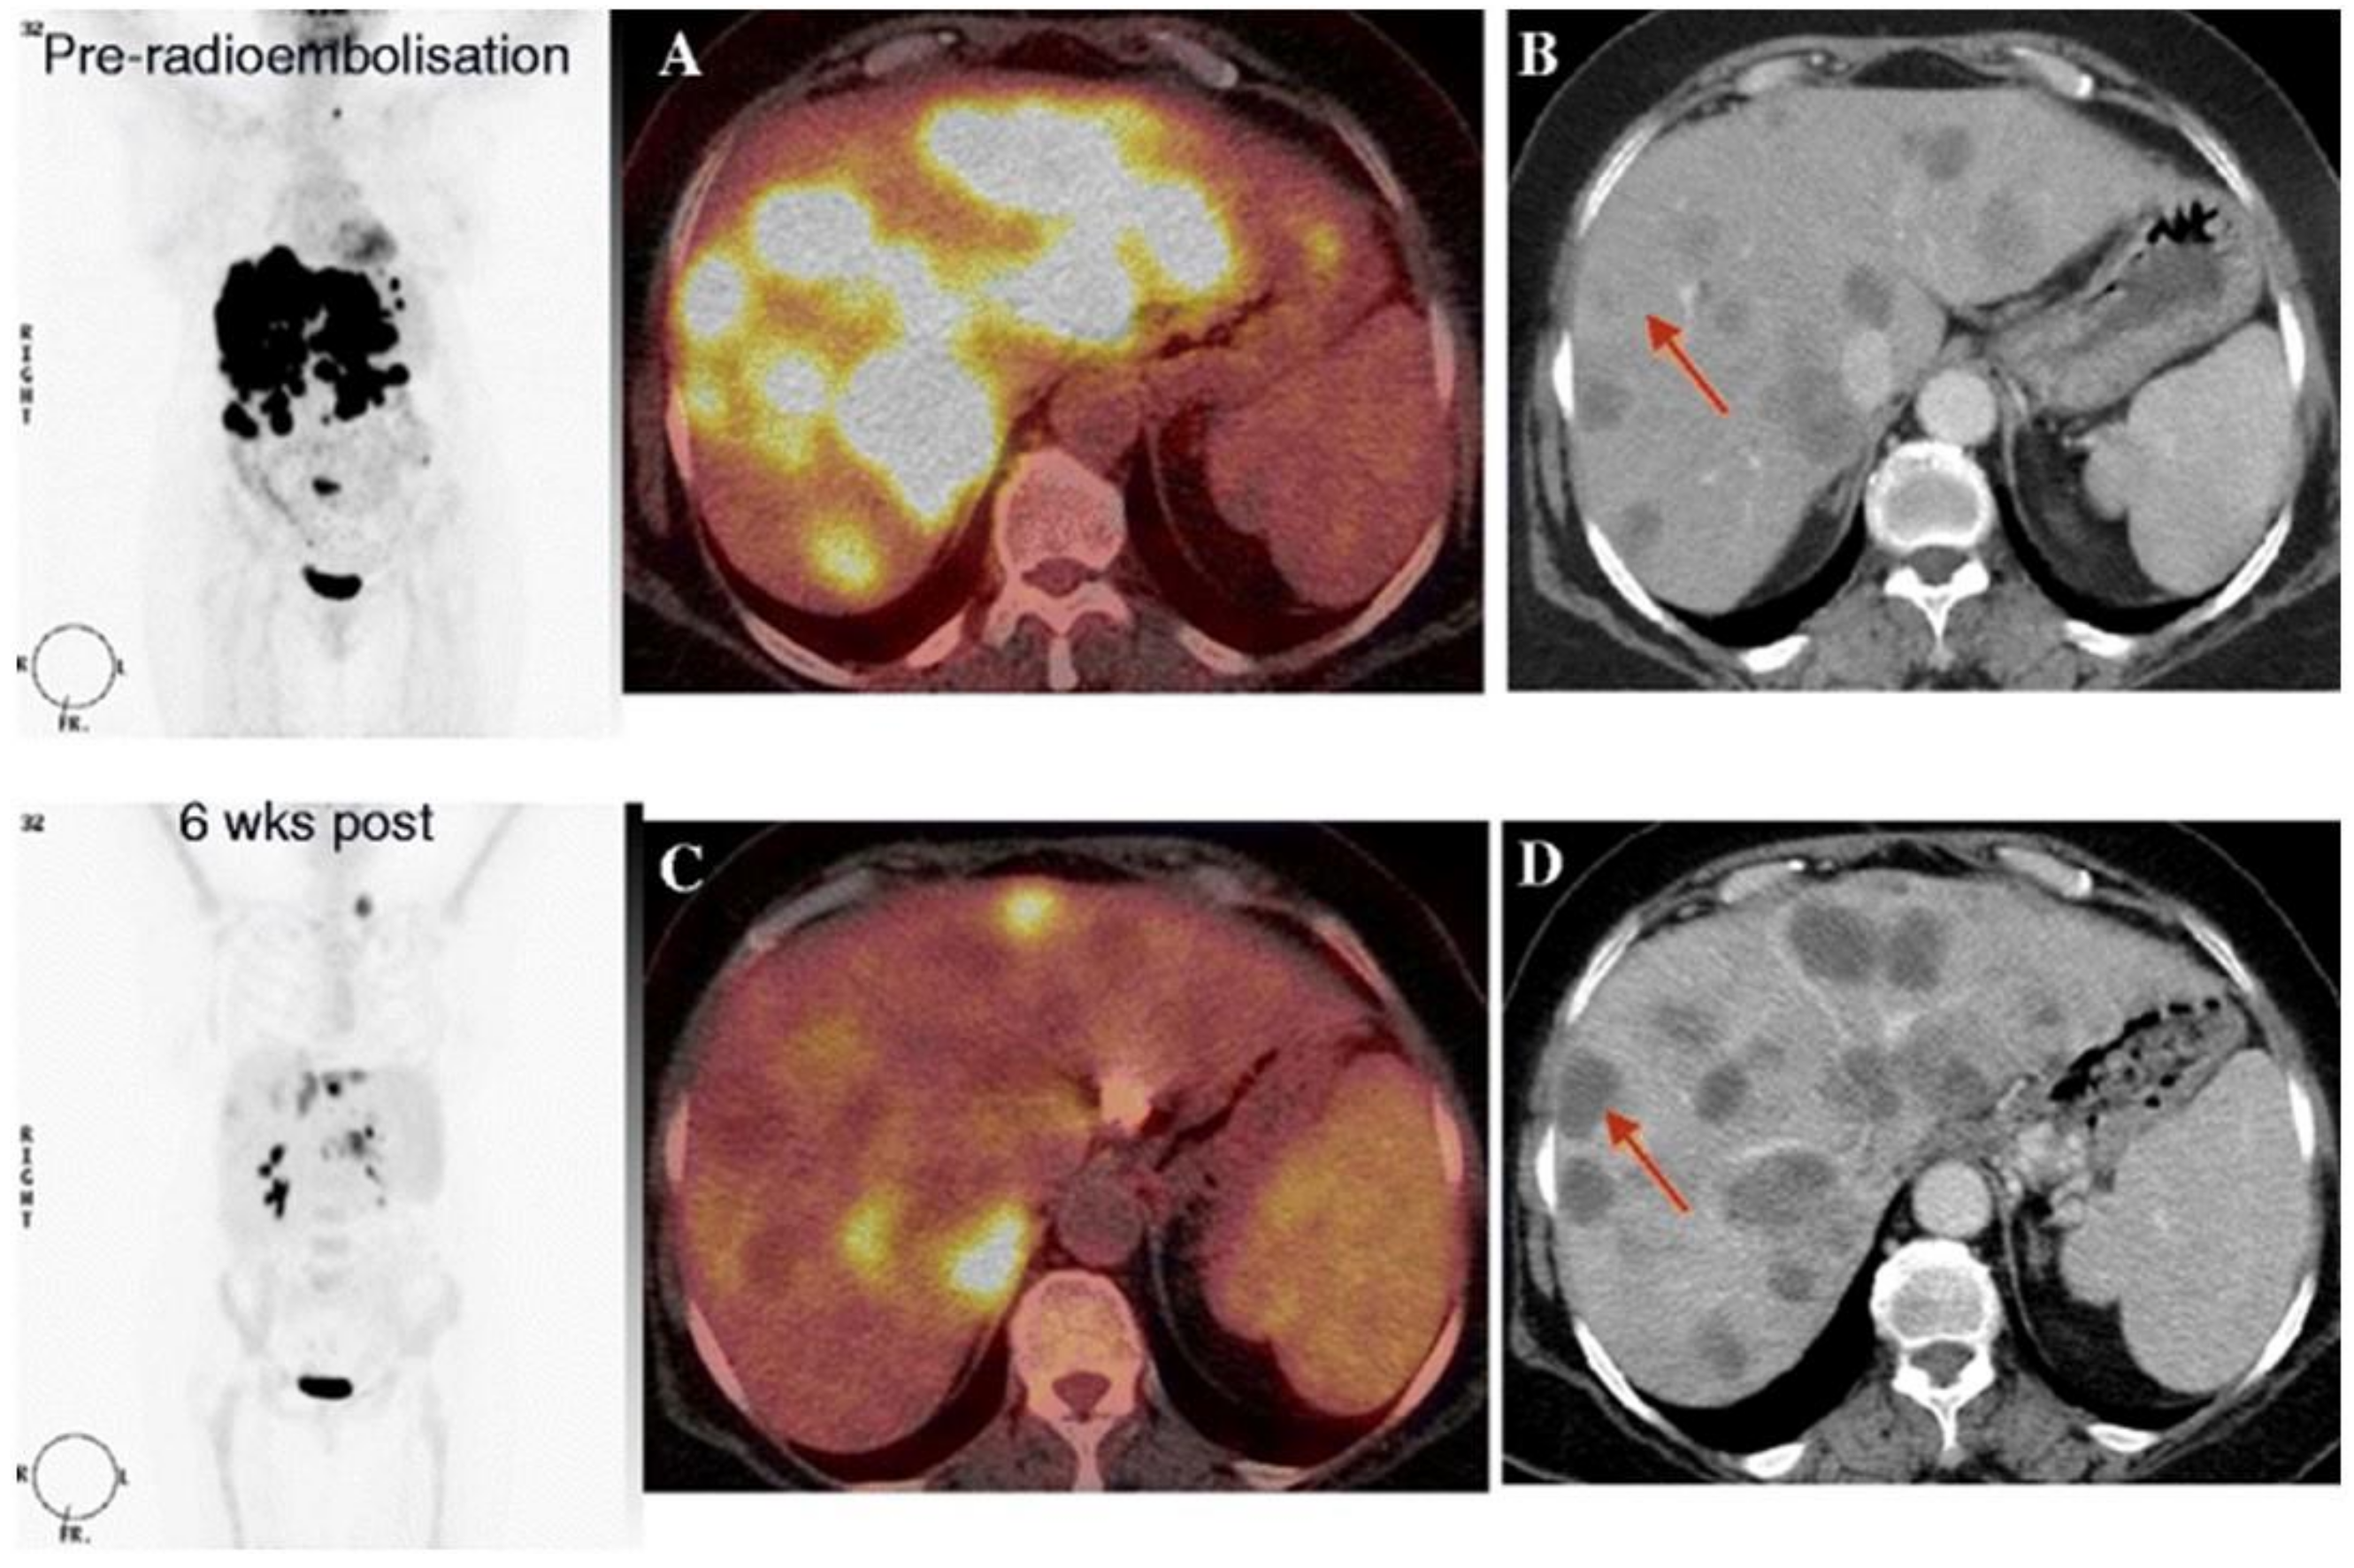

| Zerizer et al. [17] | 2012 | Retrospective | 25 | Baseline; 6–8 weeks after RE | ΔSUVmax and LTD | ceCT: RECIST 1.1 and Choi criteria | ΔSUVmax was a significant predictor of PFS, while response assessed by RECIST and tumor attenuation did not predict PFS. |

| Soydal et al. [48] | 2013 | Retrospective | 35 | Baseline; 6 weeks after RE | ΔTLG, ΔFTV and ΔSUVmax | OS | ΔTLG was not a significant predictor of OS. |

| Sabet et al. [49] | 2015 | Retrospective | 51 | Baseline; 4 weeks after RE | ≥50% ΔTLR | OS | A decrease of ≥50% of TLG was a significant predictor of prolonged OS. |

| Shady et al. [50] | 2016 | Retrospective | 25 | Baseline; <10 weeks after RE | EORTC PET criteria, Choi criteria, tumor attenuation criteria | ceCT: RECIST 1.1 | Response determined by EORTC PET criteria, Choi criteria, and tumor attenuation criteria were predictors of hepatic PFS. |

| Shady et al. [51] | 2016 | Retrospective | 49 | Baseline; <12 weeks after RE | ΔSUVmax; ΔSUVpeak; ΔMTV; ΔTLG | ceCT: RECIST 1.1 | Response by ≥30% ΔMTV and ΔTLG were significantly correlated with OS, whereas response by ΔSUVmax, ΔSUVpeak, and RECIST did not correlate with OS. |

| Jongen et al. [52] | 2018 | Prospective | 38 | Baseline; 1 month after RE; 3 months after RE | ΔLTD; ΔTLG | MRI: RECIST 1.1 | ΔTLG was more sensitive than ΔLTD for prediction of OS. |

| Sager et al. [53] | 2019 | Retrospective | 19 | Baseline; 6 weeks after RE | Mean tumor volume; µMTV | CT and/or MRI: RECIST 1.1 | PERCIST criteria are more reliable than RECIST criteria for treatment response evaluation. |